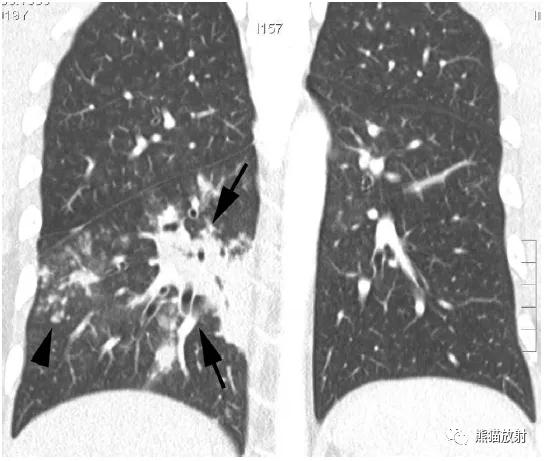

↑ 脓毒性肺栓塞 Septic embolism

40岁男性,发热,静脉注射*品毒**史。CT显示左肺多发空洞性结节,不同的血管与结节相连。血培养金黄色葡萄球菌阳性。